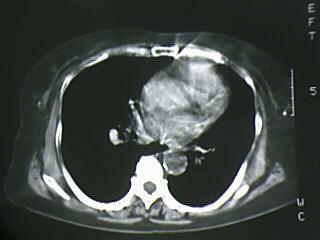

以下是引用杀毒软件在2009-4-14 17:52:00的发言:[br]考虑---右肺继发型肺结核---纵隔淋巴结多发钙化----左肺支扩

以下是引用黑白光影在2009-4-14 20:36:00的发言:[br]右肺继发型肺结核;左下慢性支气管炎性病变。